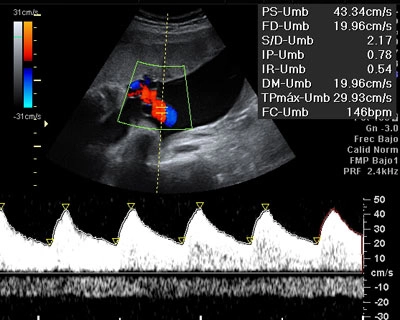

Doppler Materno Fetal

Analizamos el flujo sanguíneo entre la madre y el bebé, garantizando un adecuado suministro de oxígeno y nutrientes durante la gestación.